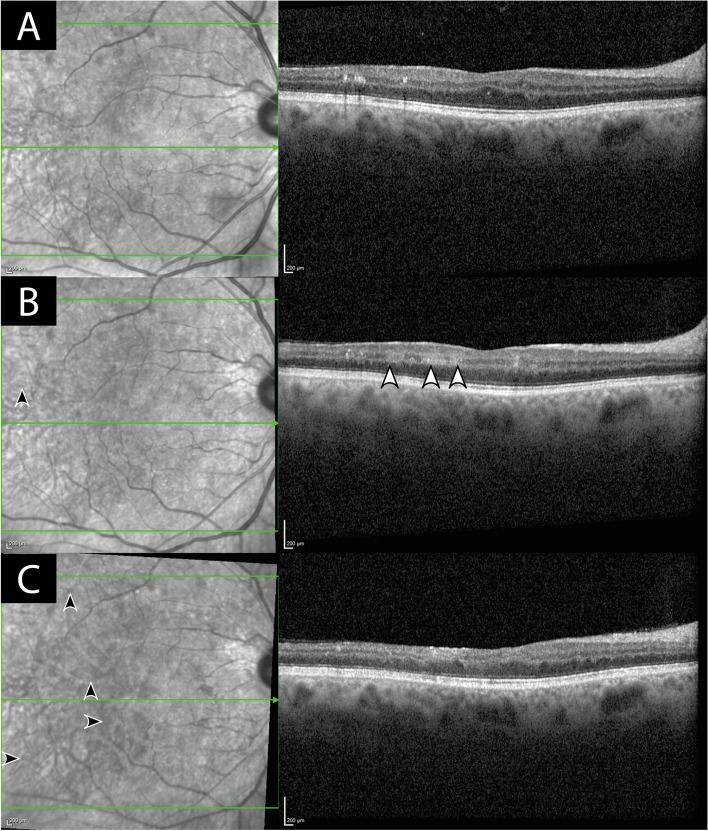

Purpose: We describe a case of occlusive vasculitis associated with intravitreal Faricimab (Vabysmo) injections.

Results: A 52-year old man treated with monthly Faricimab injections for diabetic macula oedema presented with sudden reduced vision, new retinal hemorrhages, significant retinal vascular occlusions and ischemia. After screening for differential diagnoses was unremarkable, the patient was treated with oral and intravitreal steroid therapy under which the occlusive vasculitis was stabilized.